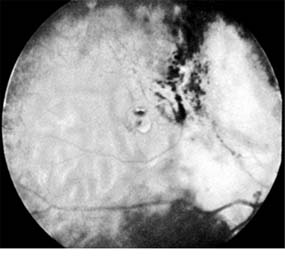

Enucleation is the treatment of choice for large retinoblastomas. Eyes with smaller tumors can be effectively treated with plaque or external beam radiotherapy (Figure 10-34), cryotherapy, or photocoagulation. Chemotherapy is being used to reduce the size of large tumors prior to other types of therapy and occasionally as the sole form of therapy. It is also used to treat tumors that have extended into the brain, orbit, or distally and may be used after enucleation in patients at high risk for such widespread disease.

Figure 10-34

Figure 10-34: Retinoblastoma after radiotherapy.